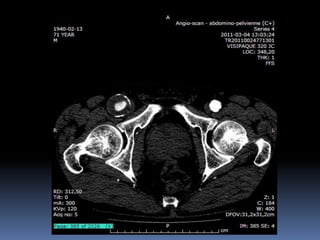

Cas #2  ♂57 ans  ATCD  Anévr. Poplité D. op ‘2000  Anévr. Poplité G. op. ‘2001  Db 2  Korsakoff  R.C. Douleurs locales à G.  Constatations…

72 59 ATCD: PABI’99 re: AIliaquebil ATCD: Db , ROH Korsakoff, MCASPAC, fempop bilat Anévr popl. Suivi Anévr fém et popl RC: référé rupture…en fait «non» mais symptomatique Quest: … Quest.:C.I. non limitante E.P.: masse puls. > 5cm ing. D non doul et autres… E.P.: masse pulsatile >5 cm ing G doul palpation, nécrose sèche extr dist un orteil non doul Pls périph N Doppler Angioscan: dimensions anévr. ? Angioscan: dimensions Anévr ?

Cas #1 72ans Cas #2 59 ans  Suivi  ATCD  PABI  Particularités  Anévrysme Fémorale profonde  Cutler-Darling type 1  Symptomatique  ATCD  Fem-pop. Bilatéraux…  Particularités  Korsakoff  Cutler-Darling type 2 thrombosés